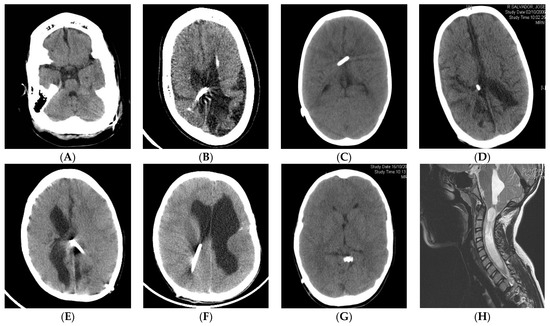

| Radiological findings | Small ventricles (moderate or normal sized also found). Extra-axial collections of fluid or blood. MRI: widened brain sulci, calcifications, etc. | Small ventricles with collapse onto the catheter tip. Occasionally with ventricular asymmetry, isolated compartments or IFV | Small ventricles. Suture sclerosis, laminated thickening, posterior fossa hypoplasia, etc. MRI: obliterated subarachnoid space, Chiari, spinal canal stenosis | Small ventricles with collapse onto the catheter tip. MRI: diffuse meningeal and arachnoid thickening, gadolinium hyperuptake, venous congestion, brain edema |